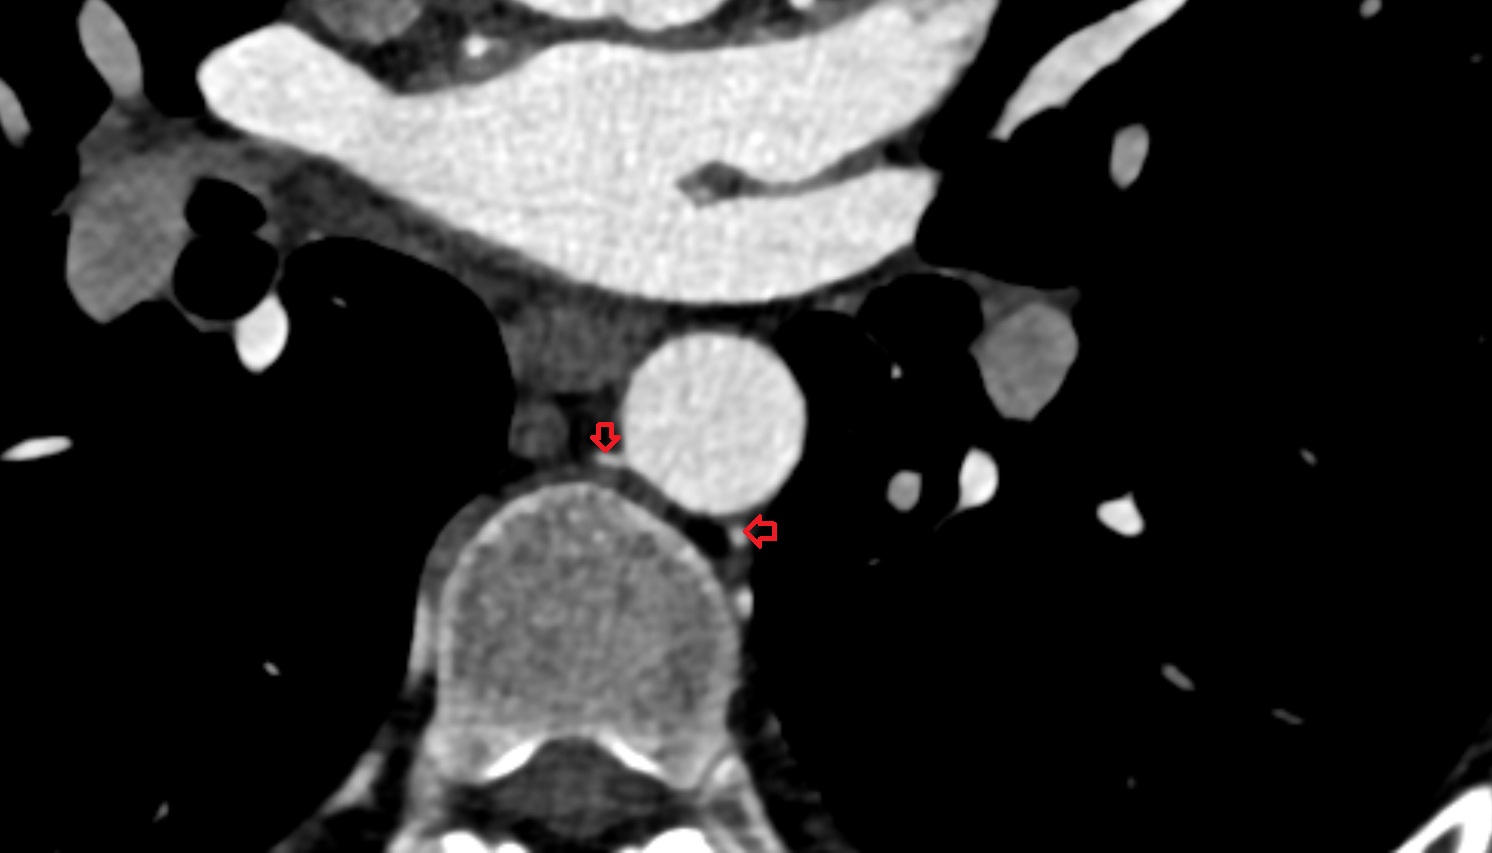

- Aortic bifurcation

- External iliac artery

- Internal iliac artery

- common iliac artery

- Abdominal aorta